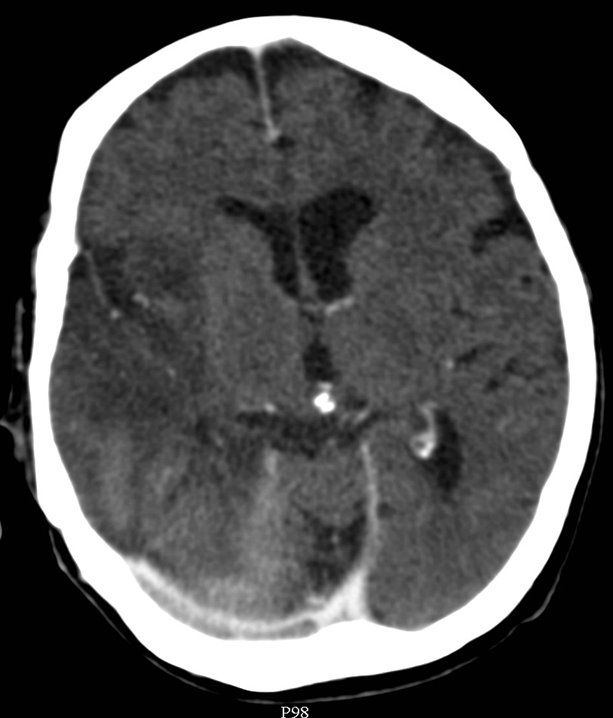

The key question whether the patient ha intracranial hematoma, which causes mass effect and later leads to vasoconstriction. In the presence of open skull fracture signed by liquorrhea severe infection and herniation might occur. To exclude intracranial hemorrhage CT is the modality of choice.

All three types of intracranial hematoma can occur as a result of head trauma:

• Rupture of the meningeal arteries may give rise to an epidural hematoma. At the site of the hematoma skull fracture can be observed.

• Subdural bleeding is caused by injured bridging veins (elongation, tears) e.g. when a sudden deceleration occurs. This type of injury generally is not associated with a fracture.

• Subarachnoid hemorrhage develops after vascular injury or aneurysm rupture.

• Contusion hemorrhage occurs upon sudden deceleration (e.g. car accident - collision) when the brain parenchyma due to its inertness keeps moving and hits the cranial bone. Frequently, contusion develops on the opposite side as well, since on an abrupt stop the brain collides with the bone than bounces off and hits the opposite wall of the skull. (coup - contrecoup effect)